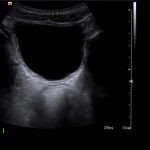

- Tubular, blind-ending structure in the right lower quadrant measuring 9 mm in diameter, which is noncompressible with mild wall thickening and mild mural hyperemia

Dilated appendix, measuring 9 mm in diameter, which is noncompressible with mild wall thickening and mild mural hyperemia, concerning for acute appendicitis.